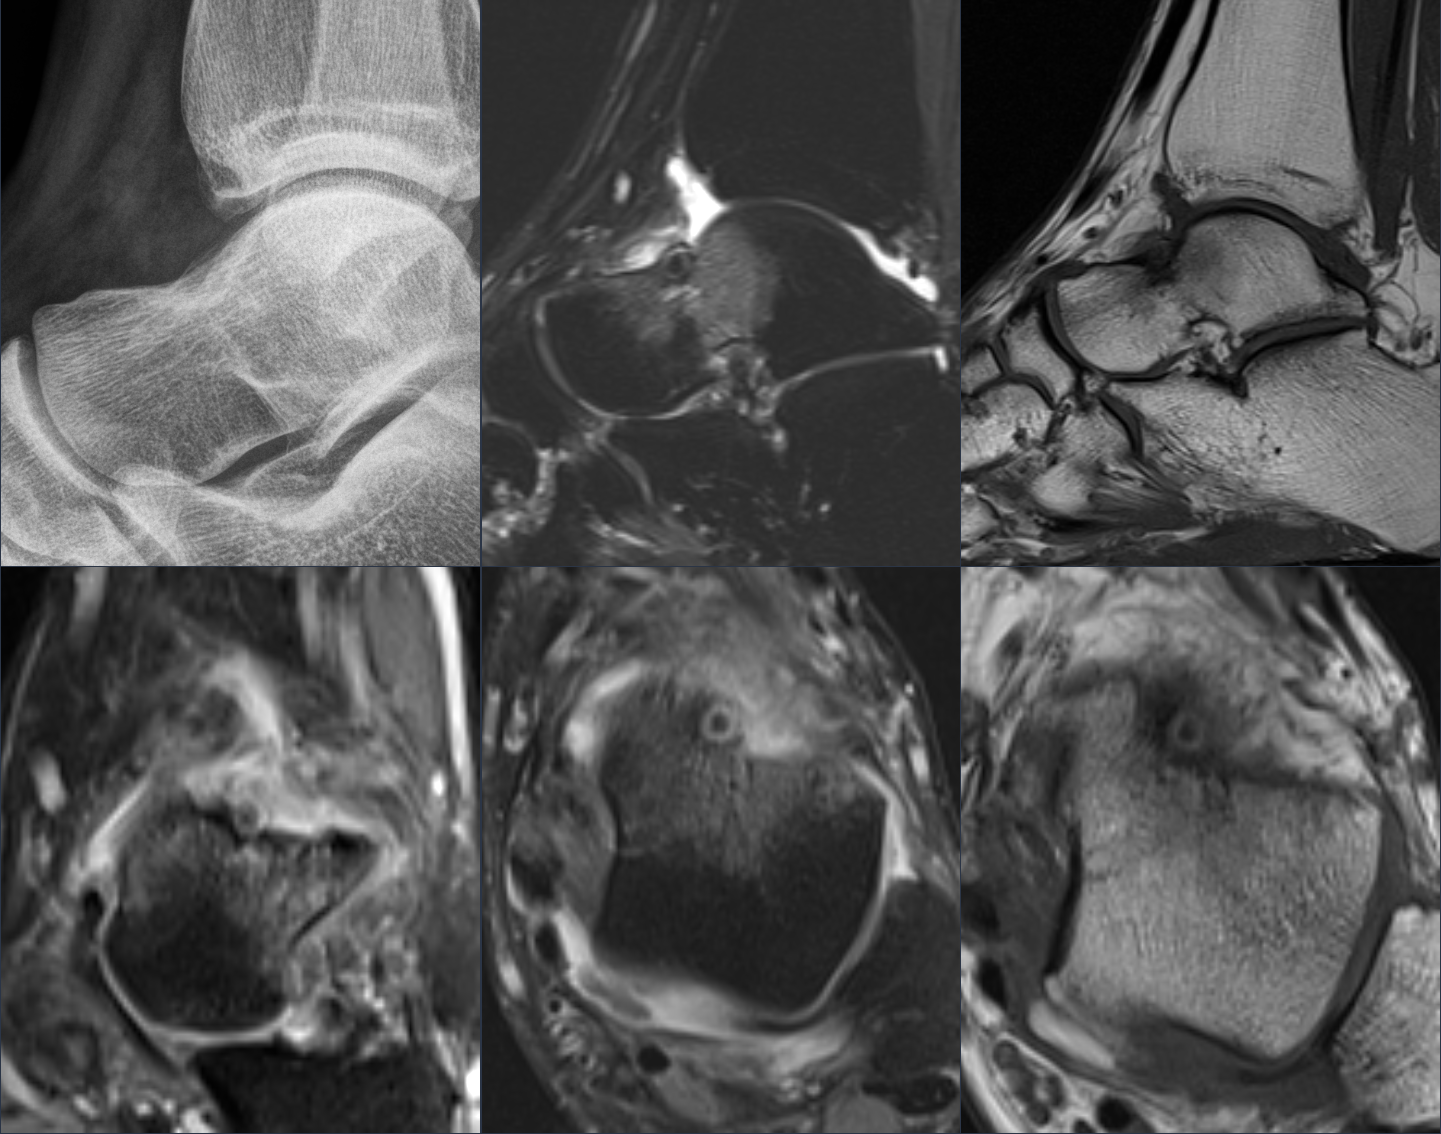

This is a 47 y/o patient with ‘left ankle injury 1 year ago ,chronic pain with limping not responding to treatment or physiotherapy’.

Probably the oldest patient with OO I have seen but another one of 5 or so I have seen in the exact same location. There must be something about this…